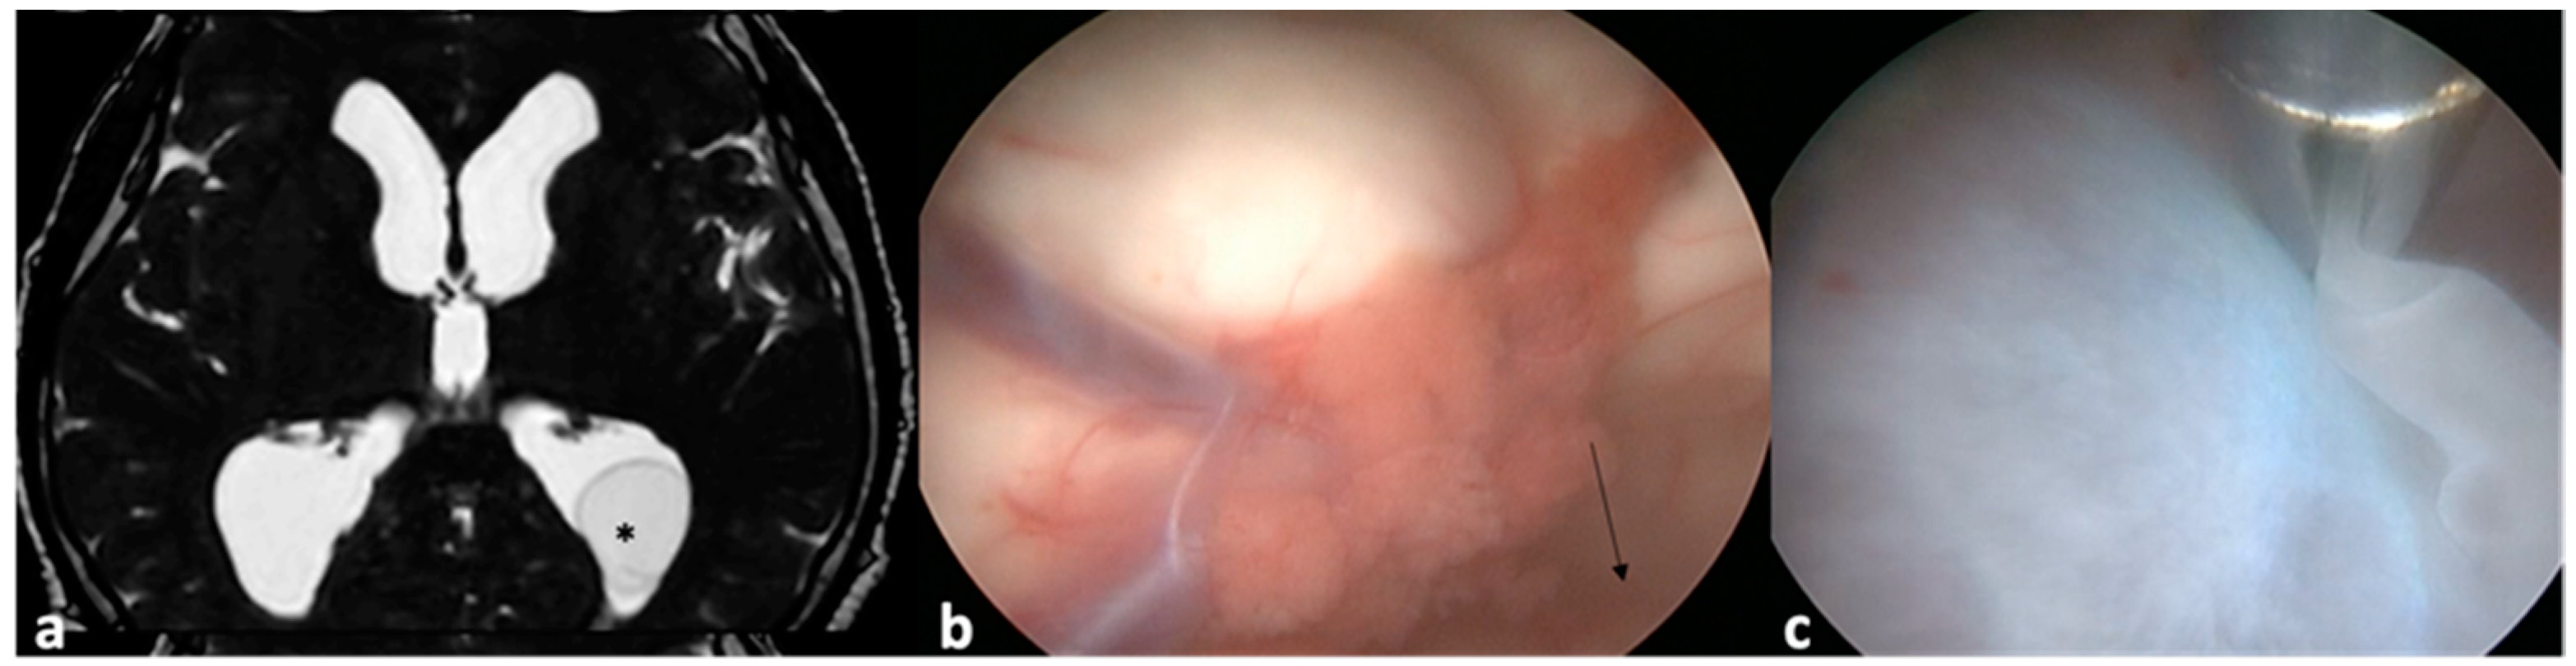

- Husain, M.; Jha, D.K.; Rastogi, M.; Husain, N.; Gupta, R.K. Neuro-endoscopic Management of Intraventricular Neurocysticercosis (NCC). Acta Neurochir. 2007, 149, 341–346. [Google Scholar] [CrossRef]

- Torres-Corzo, J.G.; Tapia-Pérez, J.H.; Vecchia, R.R.; Chalita-Williams, J.C.; Sánchez-Aguilar, M.; Sánchez-Rodríguez, J.J. Endoscopic Management of Hydrocephalus Due to Neurocysticercosis. Clin. Neurol. Neurosurg. 2010, 112, 11–16. [Google Scholar] [CrossRef] [PubMed]

- Proaño, J.V.; Torres-Corzo, J.; Rodríguez-Della Vecchia, R.; Guizar-Sahagun, G.; Rangel-Castilla, L. Intraventricular and Subarachnoid Basal Cisterns Neurocysticercosis: A Comparative Study Between Traditional Treatment Versus Neuroendoscopic Surgery. Child’s Nerv. Syst. 2009, 25, 1467–1475. [Google Scholar] [CrossRef] [PubMed]

- Goel, R.K.; Ahmad, F.U.; Vellimana, A.K.; Suri, A.; Chandra, P.S.; Kumar, R.; Sharma, B.S.; Mahapatra, A.K. Endoscopic Management of Intraventricular Neurocysticercosis. J. Clin. Neurosci. 2008, 15, 1096–1101. [Google Scholar] [CrossRef] [PubMed]

- Zhenye, L.; Chuzhong, L.; Xuyi, Z.; Songbai, G.; Peng, Z.; Jiwei, B.; Lei, C.; Xinsheng, W. Ventriculoscopic Approach for Intraventricular Neurocysticercosis: A Single Neurosurgical Center’s Experience. World Neurosurg. 2017, 107, 853–859. [Google Scholar] [CrossRef]

- Kaif, M.; Husain, M.; Ojha, B.K. Endoscopic Management of Intraventricular Neurocysticercosis. Turk. Neurosurg. 2019, 29, 59–65. [Google Scholar]

- Zymberg, S.T. Neurocysticercosis. World Neurosurg. 2013, 79, S24.e5–S24.e8. [Google Scholar] [CrossRef]

- Sharma, B.S.; Sawarkar, D.P.; Verma, S.K. Endoscopic Management of Fourth Ventricle Neurocysticercosis: Description of the New Technique in a Case Series of 5 Cases and Review of the Literature. World Neurosurg. 2019, 122, e647–e654. [Google Scholar] [CrossRef]

- Singh, S.; Marutirao, R.; Deora, H.; Das, K.K.; Bhaisora, K.S.; Sardhara, J.; Parab, A.; Mehrotra, A.; Srivastava, A.K.; Jaiswal, S.; et al. Endoscopic Route for Excision of Intraventricular Neurocysticercosis: Light At the End of the Tunnel. World Neurosurg. 2019, 125, e74–e81. [Google Scholar] [CrossRef] [PubMed]